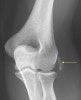

1. X-ray

외상 및 다른 질환과의 감별을 위해 촬영합니다.

약 20%에서 건의 석회화와 과상부의 반응성 외골증(exostosis)의 소견이 관찰됩니다.

X-ray : 외상과염(=테니스 엘보, Lateral epicondylitis)